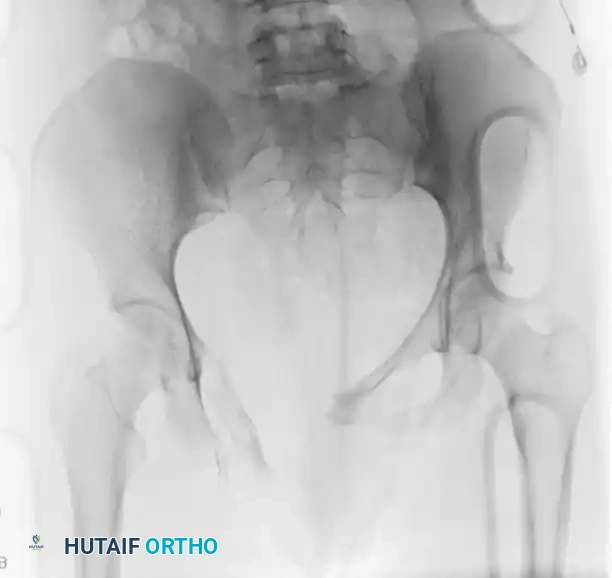

FIGURE 56-47 & 56-48: Denis classification of sacral fractures, differentiating three zones of injury: Zone I (sacral ala), Zone II (foraminal region), and Zone III (spinal canal). The most medial fracture extension classifies the injury. Accompanied by 40-degree caudal inlet and 40-degree cephalad outlet views of the pelvis.